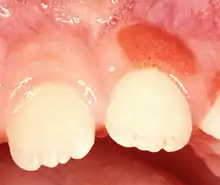

Plasma cell gingivitis

Plasma cell gingivitis[1][2] is a rare condition,[3] appearing as generalized erythema (redness) and edema (swelling) of the attached gingiva, occasionally accompanied by cheilitis (lip swelling) or glossitis (tongue swelling).[4] It is called plasma cell gingivitis where the gingiva (gums) are involved,[5] plasma cell cheilitis,[5] where the lips are involved, and other terms such as plasma cell orifacial mucositis,[5] or plasma cell gingivostomatitis where several sites in the mouth are involved. On the lips, the condition appears as sharply outlined, infiltrated, dark red plaque with a lacquer-like glazing of the surface of the involved oral area.[5]

| Plasma cell gingivitis in an adult (histologically verified). | |

Plasma cell gingivitis appears as mild gingival enlargement and may extend from the free marginal gingiva on to the attached gingiva.[6] Sometimes it is blended with a marginal, plaque induced gingivitis, or it does not involve the free marginal gingiva. It may also be found as a solitude red area within the attached gingiva (pictures). In some cases the healing of a plaque-induced gingivitis or a periodontitis resolves a plasma cell gingivitis situated a few mm from the earlier plaque-infected marginal gingiva. In case of one or few solitary areas of plasma cell gingivitis, no symptoms are reported from the patient. Most often solitary entities are therefore found by the dentist.[2]

The gums are red, friable, or sometimes granular, and sometimes bleed easily if traumatised.[6] The normal stippling is lost.[7] There is not usually any loss of periodontal attachment.[6] In a few cases a sore mouth can develop, and if so pain is sometimes made worse by toothpastes, or hot or spicy food.[7] The lesions can extend to involve the palate.[7]